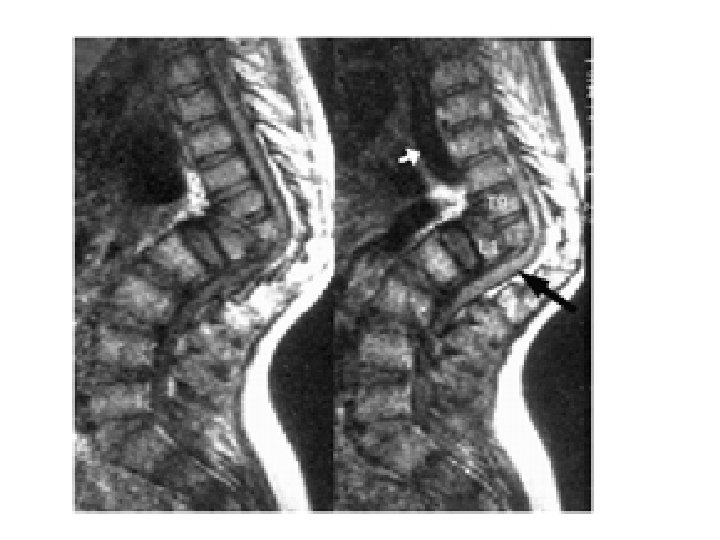

Tuberculosis of the Spine- Pott’s Disease • As a form of extrapulmonary tuberculosis that impacts the spine, Pott’s disease has an effect that is sometimes described as being a sort of arthritis for the vertebrae that make up the spinal column. More properly known as tuberculosis spondylitis, Pott’s disease is named after Dr. Percivall Pott, an eighteenth century surgeon who was considered an authority in issues related to the back and spine. Pott's disease is often experienced as a local phenomenon that begins in the thoracic section of the spinal column. Early signs of the presence of Pott’s disease generally begin with back pain that may seem to be due to simple muscle strain. However, in short order, the symptoms will begin to multiply.